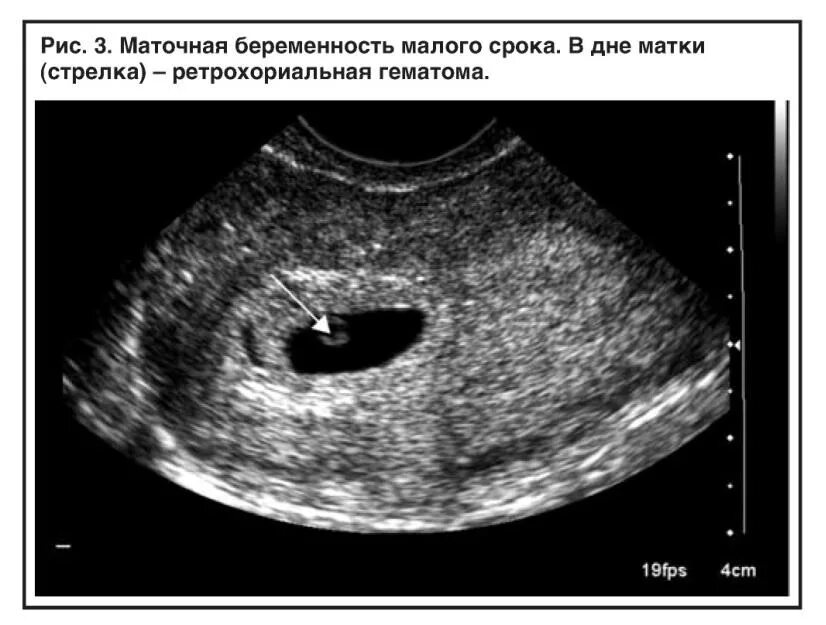

Как выходит гематома при беременности сроки